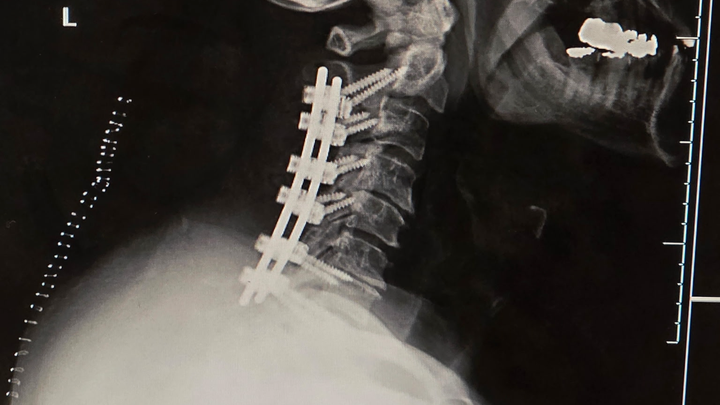

I'm embarrassed to be on here or be doing this, but I don't want to file bankruptcy and I don't want to lose everything I have and built. I had neck surgery on August 11th, and I ended up with C5, C7 & C8 Palsy from the operation. I lost total use of my left arm at the time. I've been going to therapy & working on my arm at home. While I am slowly gaining use of my arm, I've come across other medical issues. I was in the ER the other day for more blood clots in my right leg, and my lower back has gotten worse with SEVERE pain. I just had a recent MRI that confirmed that. Unfortunately, I can't do anything with my lower back until the blood clots are resolved, nor can I return to work because I don't have the strength in my left arm. Being self-employed, I don't have any means of income or disability. Like I said, I'm embarrassed to be doing this but not sure what else to do. If you donate, I thank you; if you share this, I thank you. Sincerely, Tom